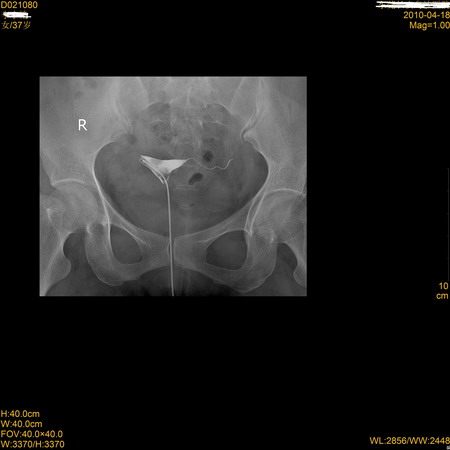

标题: X7194:右侧输卵管是怎么解释

右侧输卵管子宫部(原称角部)闭塞伴周围逆流。左侧输卵峡部闭塞。

右侧输卵管子宫部闭塞伴周围逆流。左侧输卵峡部闭塞可能。

右侧输卵管子宫部闭塞伴周围逆流,有可能是导管堵塞(第2、3张图片对比)